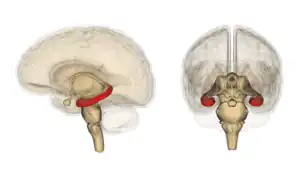

![]() El hipocampo está localizado en la parte medial del lóbulo temporal del cerebro. En esta vista lateral del cerebro humano, el lóbulo frontal está a la izquierda, el lóbulo occipital a la derecha, y los lóbulos temporal y parietal han sido retirados en gran medida para revelar el hipocampo subyacente. | ||

Se trata de una estructura marginal y de estructura de capas más sencilla de la misma sustancia gris cortical del lóbulo temporal. Por ello pertenece, por una parte al sistema límbico y por otra a la arquicorteza, componiendo junto al subículo y el giro dentado la llamada formación hipocampal. Al igual que el resto de la corteza cerebral es una estructura pareada, con dos mitades que son imágenes especulares en ambos hemisferios cerebrales. Tanto en humanos como en otros primates, el hipocampo se localiza en el interior de la parte medial o interna del lóbulo temporal, bajo la superficie cortical. La forma de caballito de mar es típica de primates, pero en otros mamíferos tiene formas variadas, como la del plátano.

El hipocampo en su conjunto tiene forma de un tubo curvado, cuyo aspecto recordó a los anatomistas formas tan variadas como la del caballito de mar, el cuerno de un carnero o del dios Amón (el Cornu Ammonis actualmente designa una parte del hipocampo que comprende las divisiones entre CA1 y CA4), y también una banana.[29] Comprende porciones ventrales y dorsales, compartiendo ambas una composición similar, pero siendo partes de diferentes circuitos neurales.[31]